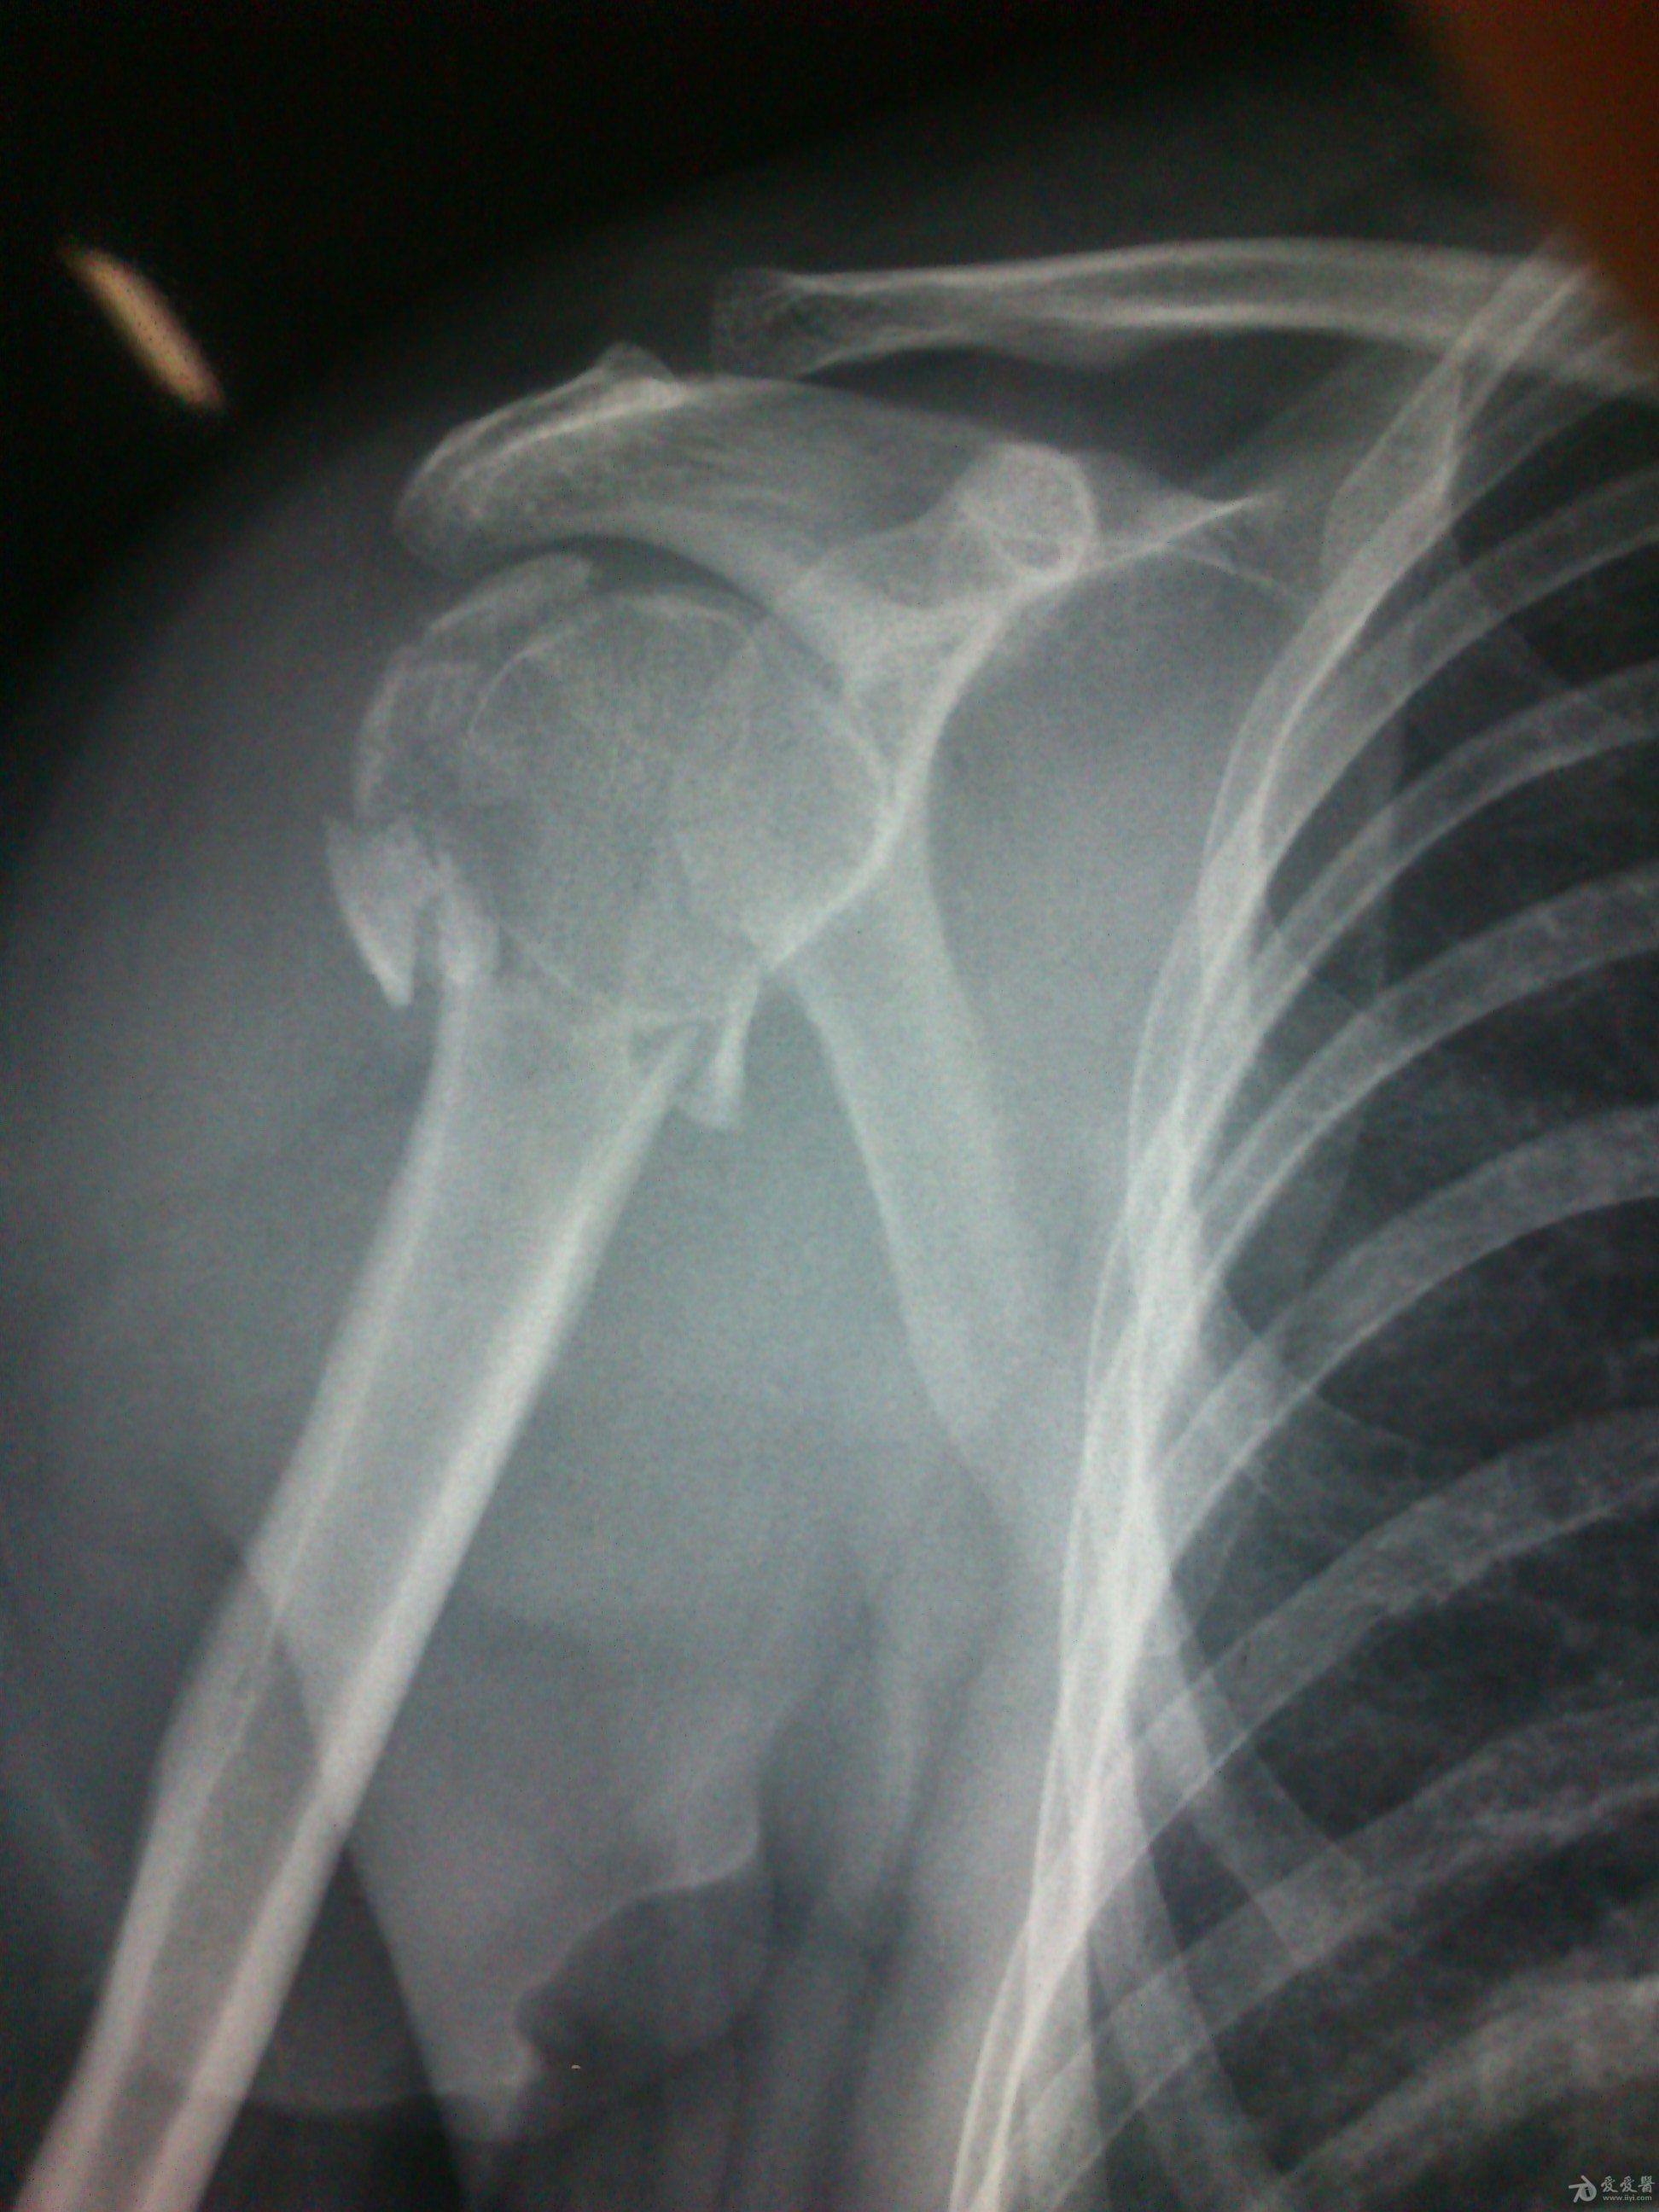

患者:女,51岁,患者因右肱骨外科颈骨折术后右肩疼痛、活动障碍1年余于2012-11-21 14:58:33由步行入院。

病史特点及病情摘要:1、患者女性,51岁。2、患者自诉入院前1年余因右肱骨外科颈骨折在外院行切开复位内固定术,术后右肩关节疼痛、活动受限,一直未予处理,今为明确诊治入院。患者精神、食欲、睡眠尚可。3、既往史、个人史、家族史无特殊。4、入院查体:生命征平稳,心肺腹检查未见异常,NS(-)。专科情况:右上臂近端内侧见一约15cm手术切口疤痕,愈合佳,右肩关节能外展20度,前屈、后伸及旋前、旋后功能障碍,余关节活动好。舌质红,苔薄白,脉实。5、辅助检查:右肩关节正侧位片:右肱骨外科颈骨折内固定术后再骨折伴右肩关节脱位。

诊断:右肱骨外科颈骨折内固定术后再骨折伴右肩关节脱位

诊疗计划:????前两张片是院外术前,中间两张是院外术后,后两张是在我院照。 术前

术前